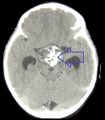

يمكن للطبيب إجراء بعض الفحوصات والاختبارات لتشخيص الشخص المصاب بالورم القحفي البلعومي.[19] يعد التصوير بالرنين المغناطيسي عالي الدقة (MRI) ذا قيمة لأنه يسمح لأخصائي الأشعة العصبية بمشاهدة الورم من زوايا مختلفة..

في بعض الحالات ، يمكن أن يساعد ماسح التصوير بالرنين المغناطيسي القوي 3T (Tesla) في تحديد موقع هياكل الدماغ الهامة المتأثرة بالورم. يتكون النمط النسيجي من تعشيش ظهارة حرشفية تحدها خلايا مرتبة بشكل اشعاعي. غالبًا ما يكون مصحوبًا بترسب الكالسيوم وقد يكون له بنية حليمية مجهرية. يعد التصوير المقطعي المحوسب (CT) أيضًا أداة تشخيصية جيدة ، حيث يكتشف التكلس في الورم..[20]

في النوع المينائي ، تظهر التكلسات في التصوير العصبي وهي مفيدة في التشخيص.